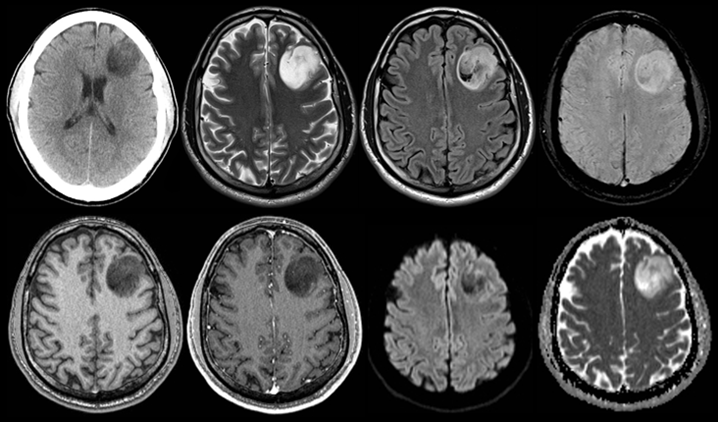

Test yourself with these two Cases of the Week